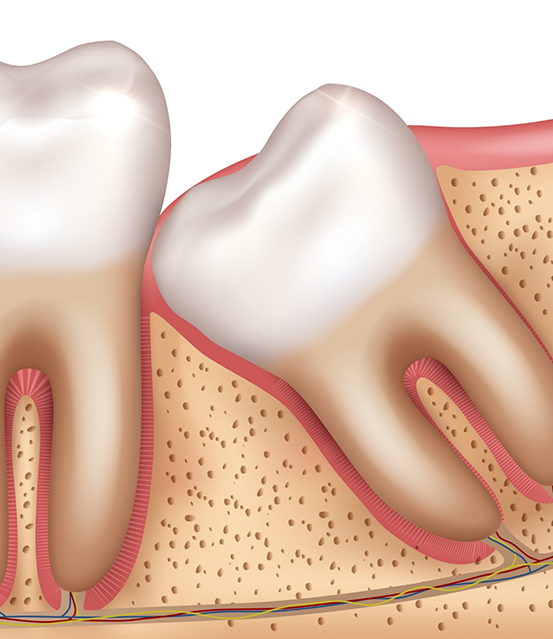

Wisdom teeth, or third molars, can erupt in your late teens and early twenties. Sometimes, these molars do not have enough room to come in properly. It might lead to crowding and infection. Here are some common reasons to get it removed:

- A trapped or partially erupted wisdom tooth can push against your neighboring teeth. You might experience swelling, chronic discomfort, and cysts if left untreated.

- The third molars can damage or shift your second molars. Lack of enough space might lead to root damage and alignment problems.

- Partially erupted teeth are challenging to clean. So they become easy targets for bacterial buildup and gum problems. Removing them can keep your mouth healthy.

Our office offers you both simple and complex extractions. We also offer services to remove a fully bony impacted tooth that has not emerged from the gums.